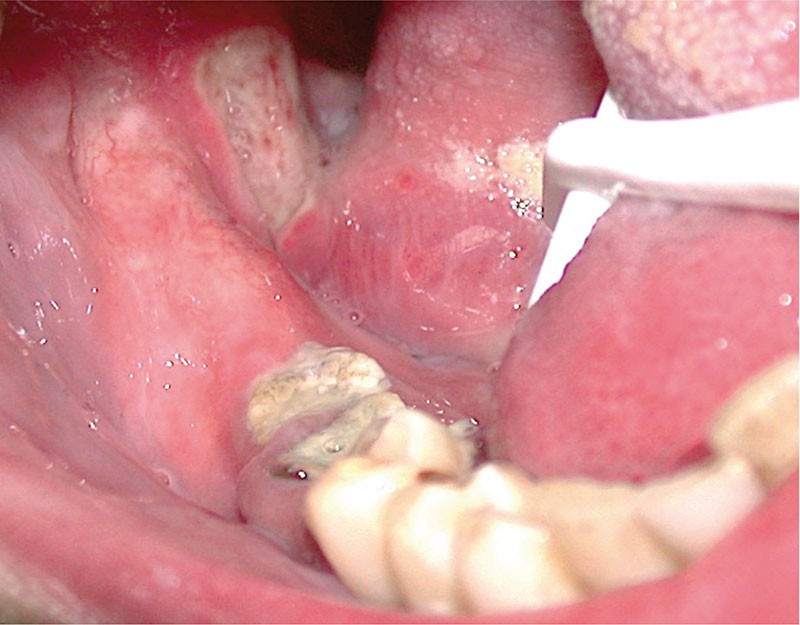

Les aphtes sont des ulcérations de la muqueuse buccale spécifiques, secondaires à une vasculite leucocytoclasique. Les aphtes buccaux sont sporadiques ou récurrents dans l’Aphtose Bucco-Pharingée Récidivante (ABPR). La forme clinique la plus sévère de l’ABPR est la grande aphtose de Touraine plus connue sous le nom de maladie de Behcet.